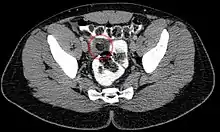

Epiploic appendagitis in computed tomography.

Abdominal CT scan, Epiploic Appendagitis (circle)

Ultrasound and CT scans are the normal means of positive diagnosis of Epiploic Appendagitis. Ultrasound scans show "an oval, non-compressible hyperechoic mass with a subtle hypoechoic rim directly under the site of maximum tenderness".[4] Normally, epiploic appendages cannot be seen on CT scan.[4] After cross-sectional imaging and the increased use of abdominal CT for evaluating lower abdominal pain, EA is increasingly diagnosed. Pathognomonic CT scan data represent EA as 2–4 cm, oval shaped, fat density lesions, surrounded by inflammation. Contrasting with diverticulitis findings, the colonic wall is mostly unchanged.